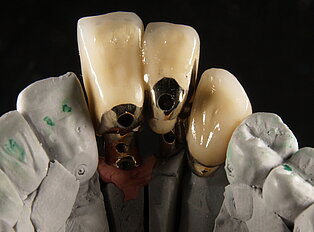

Keine Metalle im Mund